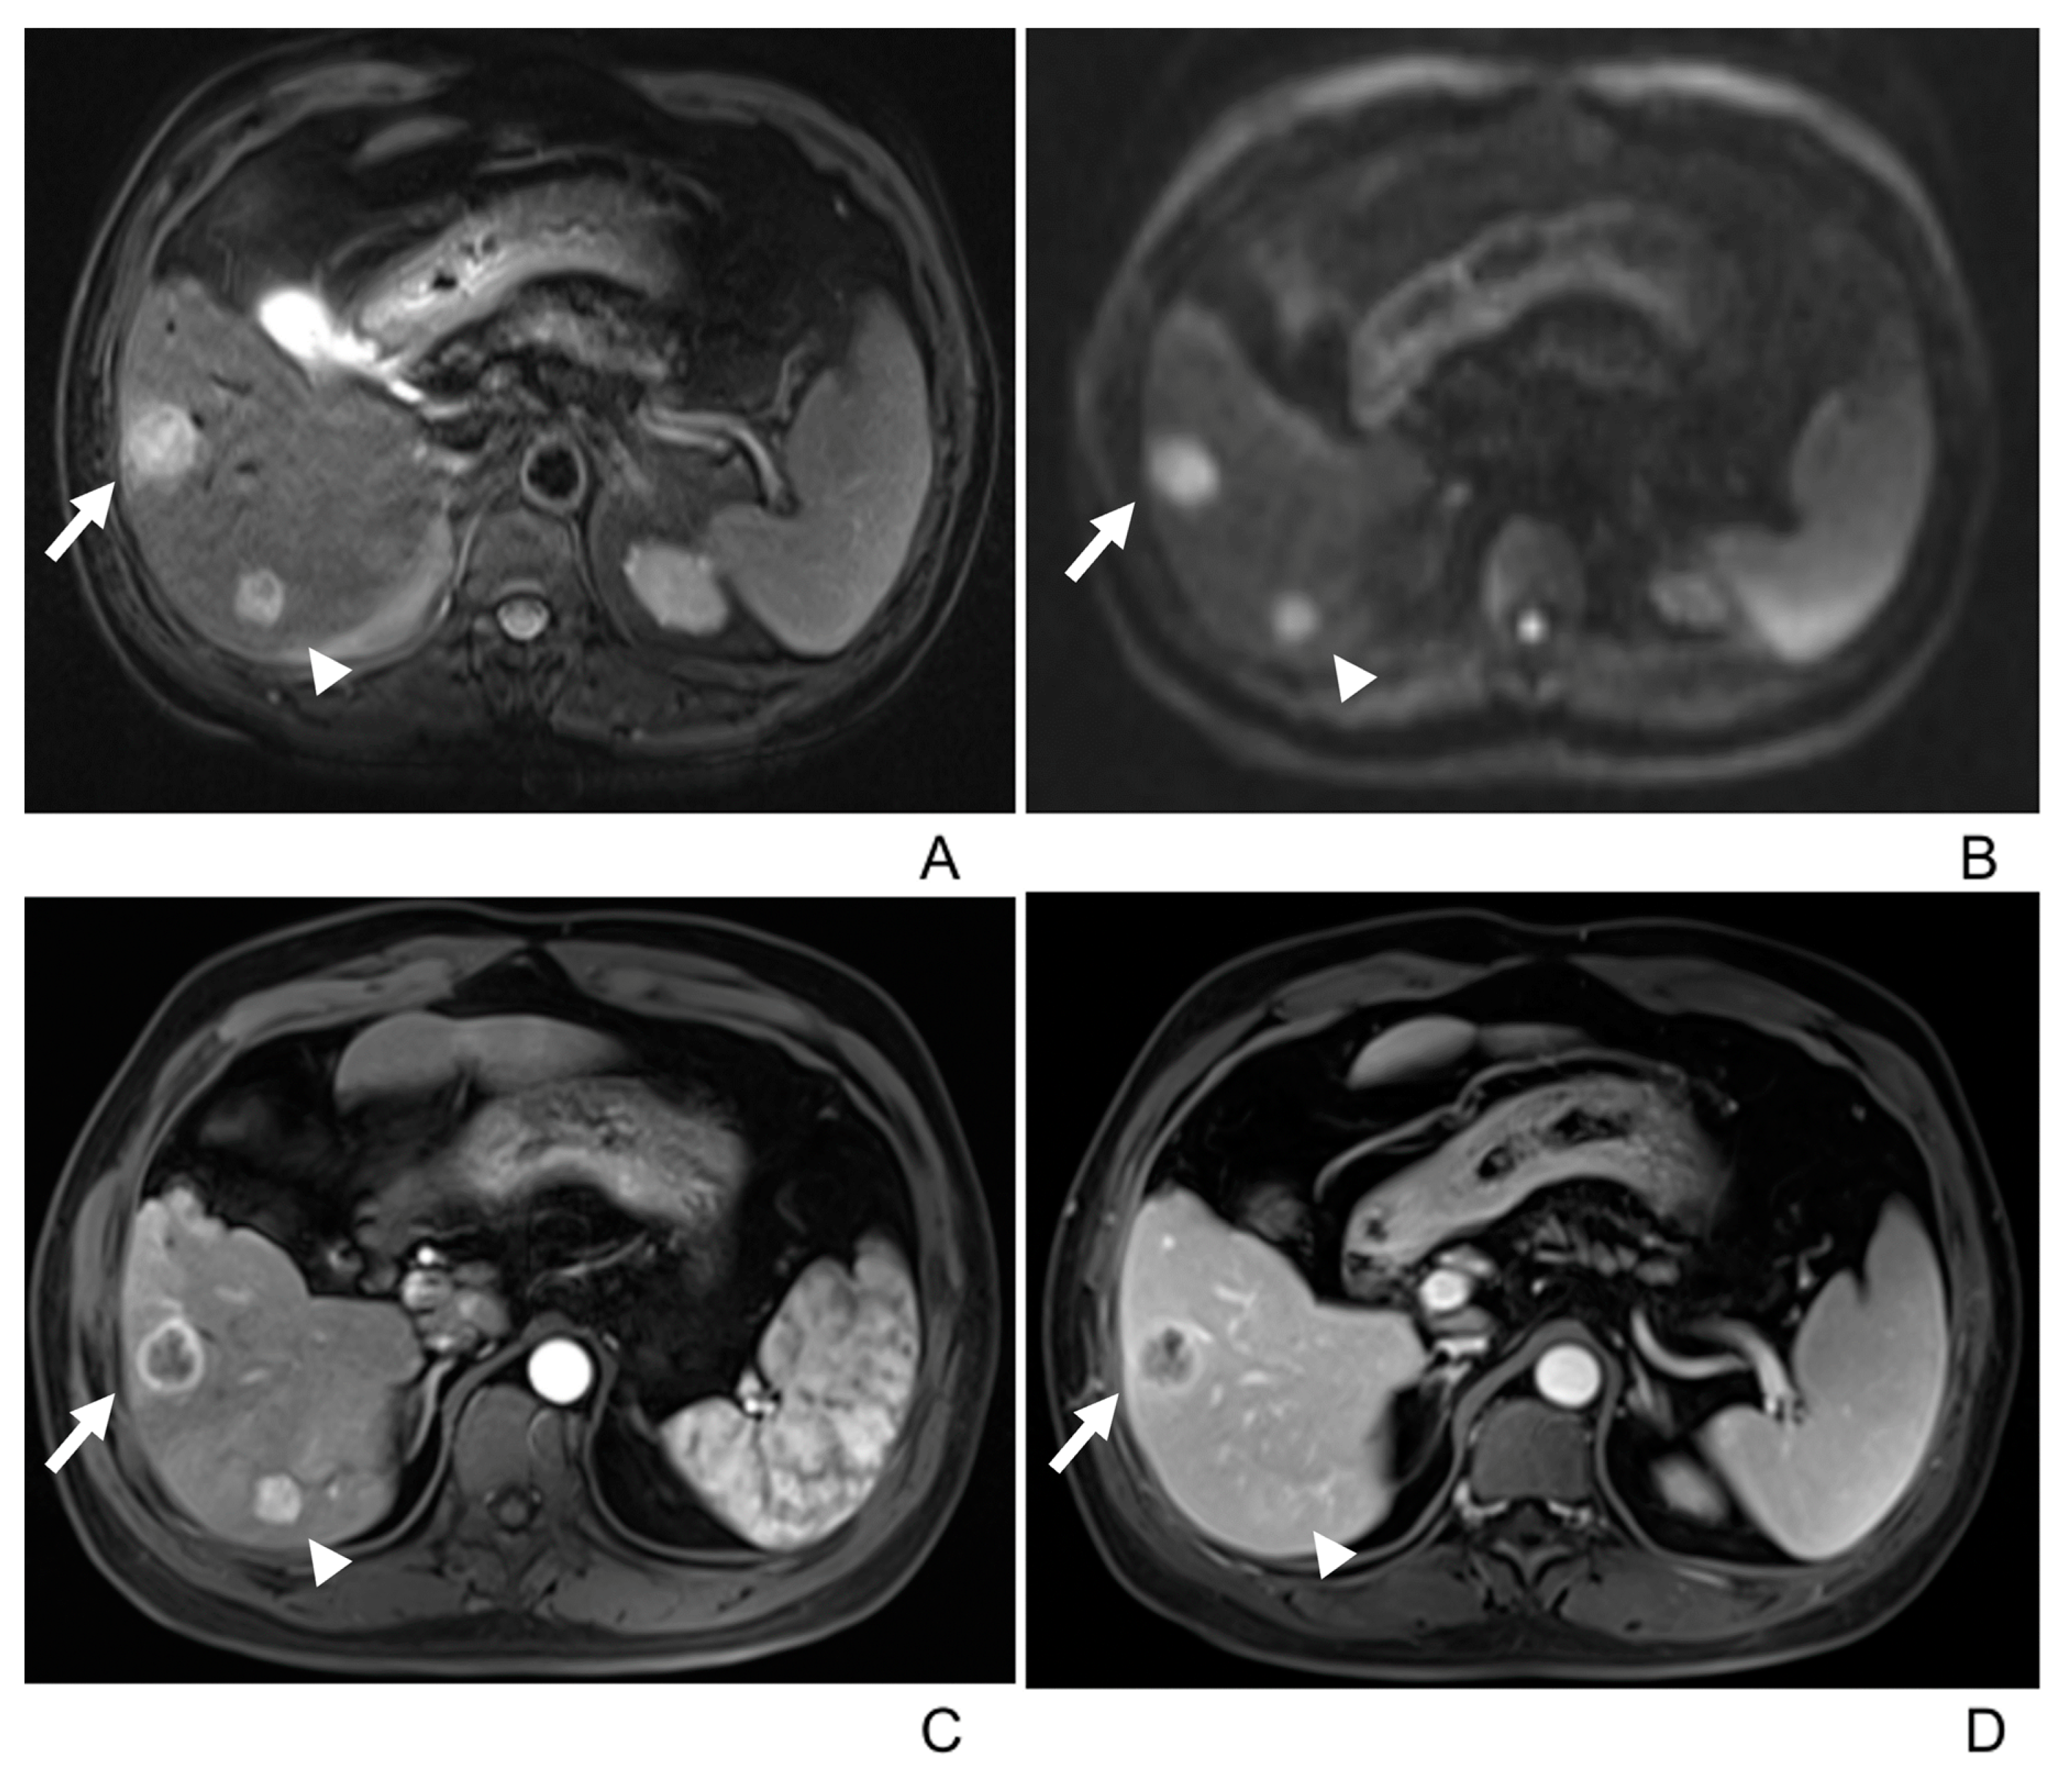

- Two tumors had associated satellite lesions.

| Lobulated | 17 (45%) |

| ADC value of lesions (mm2/s) | 1070 ± 255 |

| ADC value of liver (mm2/s) | 1335 ± 351 |

| p = 0.001 (<0.05) | |

| Satellite lesion | 2/38(6%) |